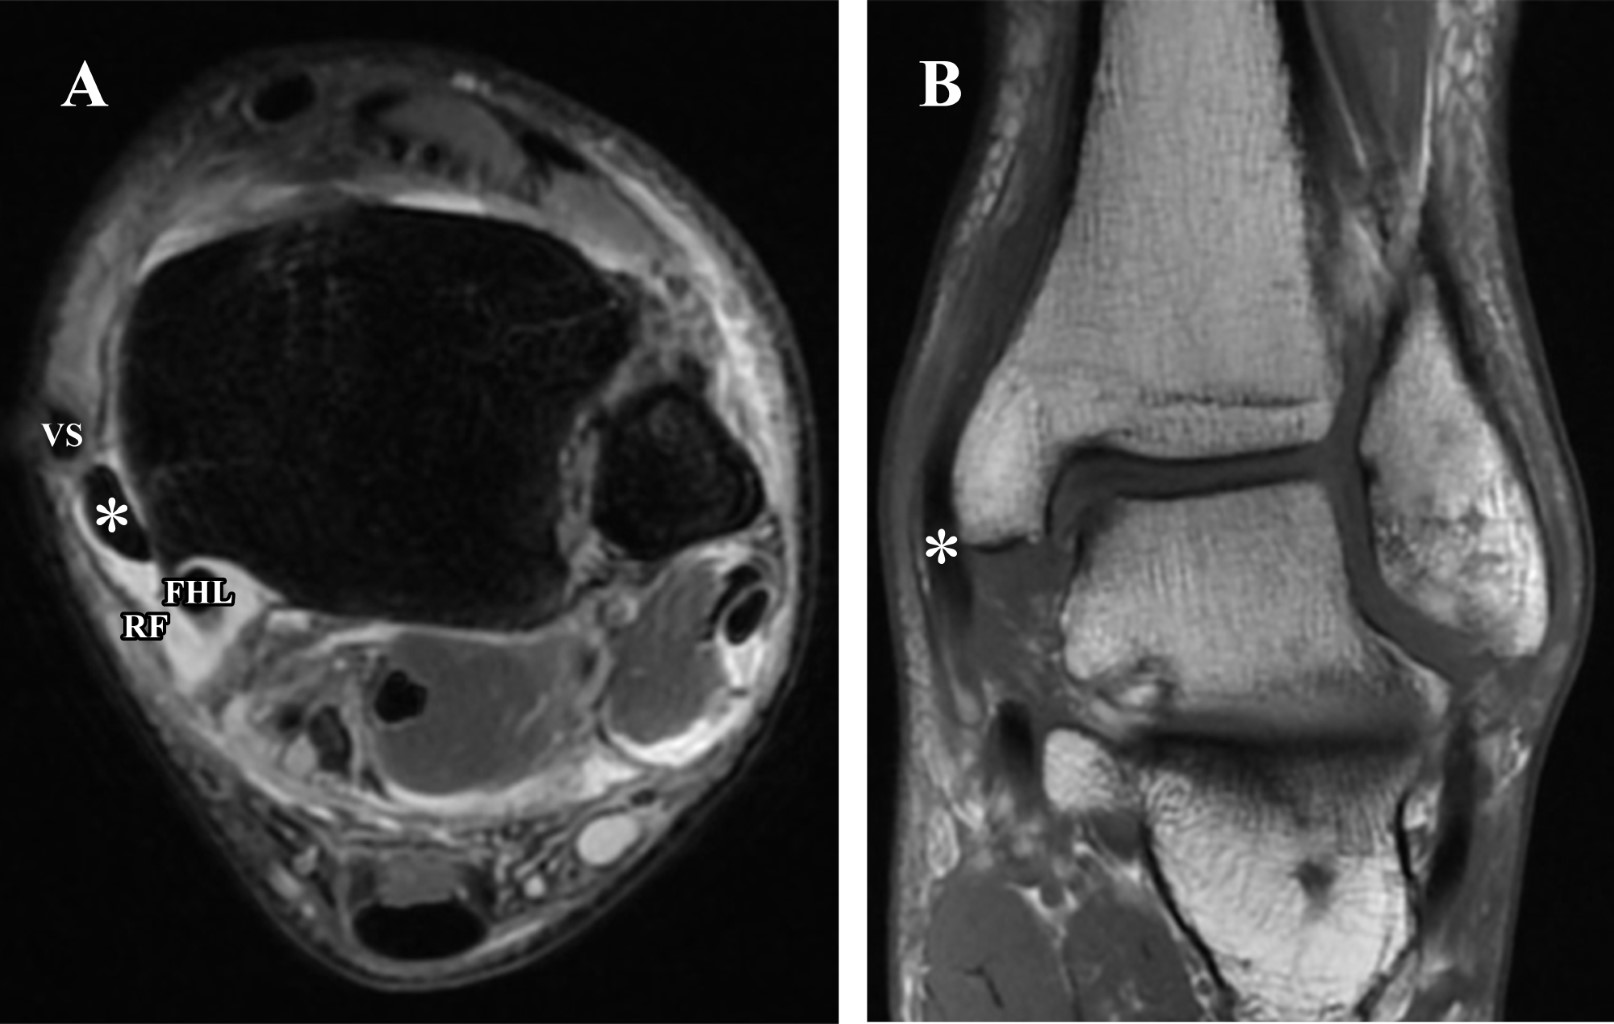

Tras la mejoría de tumefacción de partes blandas, el mismo paciente en su domicilio realizó autoexploración de tobillo palpando estructura tubular móvil a nivel de la cara medial del tobillo y dolor al intentar realizar inversión del pie. Volvió a acudir a Urgencias y se indicó la realización de una resonancia magnética para ampliar estudio (Figura 1).

En la imagen de resonancia magnética se apreció una avulsión del retináculo flexor con luxación del tendón tibial posterior asociado a ruptura parcial del ligamento deltoideo, ruptura completa de ligamento peroneoastragalino anterior y ligamento peroneocalcáneo, fractura-avulsión del ligamento tibioperoneo anterior y lesión osteocondral de la cúpula astragalina.